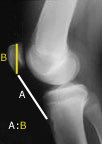

It is very difficult to measure how much shortening has occurred in the quadriceps tendon. The surgeon can get an idea if he or she can only flex the knee ninety to a hundred degrees for example. However, one can measure the amount of patellar tendon shortening using a method we published many years ago. A lateral x-ray is obtained of both knees and the height of the patella is measured, which allows interpretation of the length of the patellar tendon. The measurement of the involved knee is compared with the opposite knee, and the resulting difference indicates the amount of patella infera present.